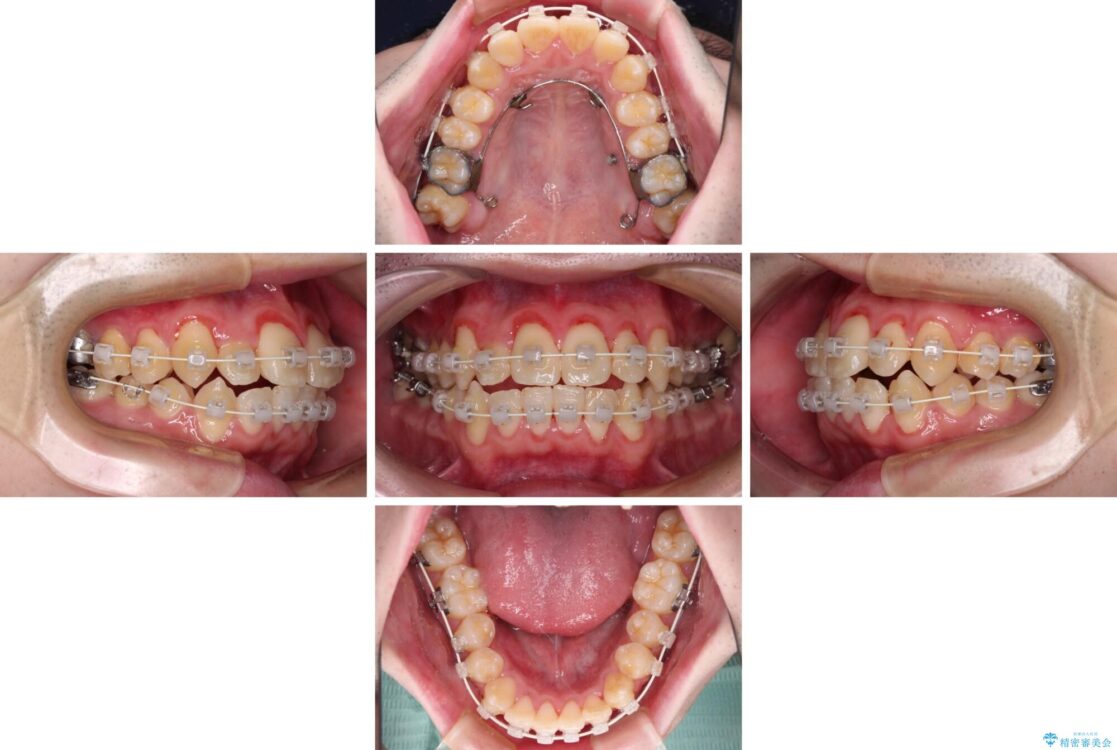

治療途中

• 全顎的なクロスバイト 補助装置を用いてワイヤー矯正 治療途中画像